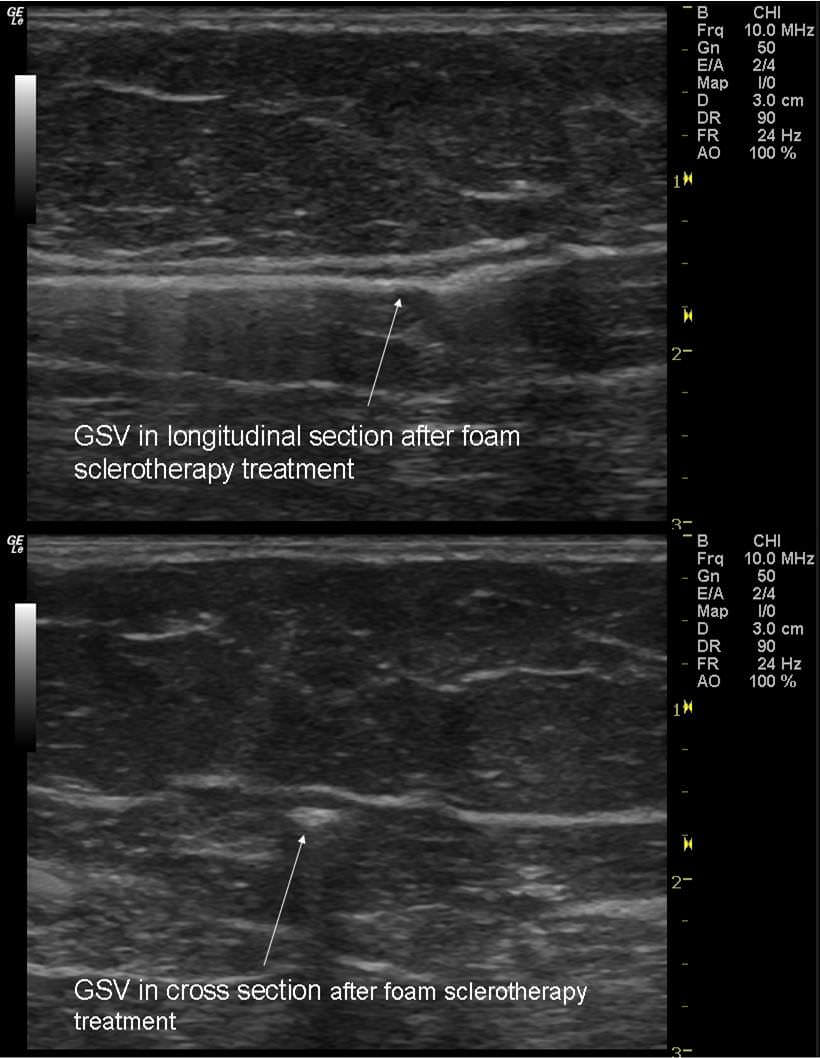

Склерозирующая терапия

Химический склероз варикозных вен с конца 1800-х годов все меньше используется. Современные склерозанты с приемлемой степенью риска стали широко доступны в 1930-х годах, и с тех пор их сфера задействования расширилась. Первоначально склеротерапия применялась в качестве хирургического вспомогательного средства после сафенэктомии для лечения остаточных варикозов, ретикулярных вен или телеангиэктазий. В настоящее время метод используется для лечения БПВ и основных притоков.

Склерозирующее вещество вводится в аномальные сосуды для стимуляции эндотелиальных разрушений. За этим следует образование фиброзного тяжа и возможная реабсорбция всех сосудистых тканевых слоев.